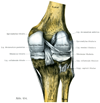

2. 自由下肢骨の結合